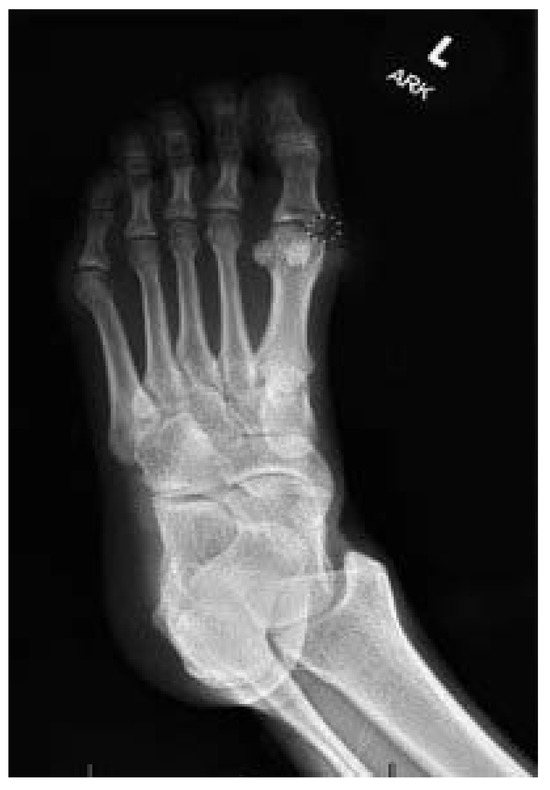

Reconstruction of a Neglected, Extensor Hallucis Longus Tendon Rupture Using Interposed Scar Tissue: A Case Report and Literature Review

by Woo-Jong Kim, Ki-Jin Jung, Hyein Ahn, Eui-Dong Yeo, Hong-Seop Lee, Sung-Hun Won, Dhong-Won Lee, Jae-Young Ji, Sung-Joon Yoon and Yong-Cheol Hong

Injury of the extensor hallucis longus (EHL) tendon is relatively rare, but surgical repair is necessary to prevent deformity and gait disturbance. Primary suturing is possible if the condition is acute, but not when it is chronic. The scar tissue between the ruptured [...] Read more.

Injury of the extensor hallucis longus (EHL) tendon is relatively rare, but surgical repair is necessary to prevent deformity and gait disturbance. Primary suturing is possible if the condition is acute, but not when it is chronic. The scar tissue between the ruptured ends is a proliferative tissue composed of fibroblasts and collagen fibers. Given the histological similarity to normal tendons, several studies have reported tendon reconstruction using scar tissue. Here, we report a reconstruction of a neglected EHL rupture using interposed scar tissue. A 54-year-old female visited our clinic with a weak extension of a big toe. She had dropped a knife on her foot a month prior, but did not go to hospital. The wound had healed, but she noted dysfunctional extension of the toe and increasing pain. Magnetic resonance imaging (MRI) revealed that EHL continuity was lost and that the proximal tendon stump was displaced toward the midfoot. Scar tissue running in the direction of the original ligament was observed between the ruptured ends. In the surgical field, the scar tissue formed a shape similar to the extensor tendon. Therefore, we performed tendon reconstruction using the interposed scar tissue. For the first 2 postoperative weeks, the ankle and foot were immobilized to protect the repair. Six weeks after surgery, the patient commenced full weight-bearing. At the 3-month follow-up, active extension of the hallux was possible, with a full range of motion. The patient did not feel any discomfort during daily life. Postoperative MRI performed at 1 year revealed that the reconstructed EHL exhibited homogeneously low signal intensity, and was continuous. The AOFAS Hallux Metatarsophalangeal-Interphalangeal scale improved from 57 to 90 points and the FAAM scores improved from 74% to 95% (the Activities of Daily Living subscale) and from 64% to 94% (the Sports subscale). Scar tissue reconstruction is as effective as tendon autografting or allografting, eliminates the risk of donor site morbidity and infection, and requires only a small incision and a short operative time. Full article